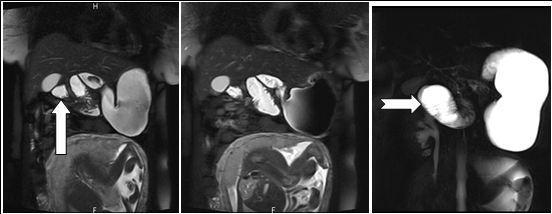

Figure 3.Coronal reformatted image shows contrast agent–filled small bowel on right

In that aspect, small bowel volvulus should always remain in the differential diagnosis in front of a pregnant woman presenting with abdominal pain during pregnancy, especially one like ours that was known for a previous surgery for appendicitis (a possible reason for the presence of the adhesions). Radiologic diagnosis of small bowel volvulus can be done by several technics. Plain abdominal film can be used, showing sometimes a typical pattern of dilated loops, but more often showing a normal radiological pattern due to a proximal position of the volvulus (with the loops being filled with liquid). Evidences on CT-scan are the presence of dilated bowel loops, intramural gas and the “whirlpool sign” (Cong et al, 2014; Shui et al, 2011)4, 12, but the use of technics exposing the foetus to radiations is debated. However, in their review, Cong et al 4emphasized the fact that those technics (and particularly plain radiography) are considered safe for the mother as well as for the foetus (Cong et al, 2014)4. MRI is also safe and extremely precise in the diagnosis of small bowel obstruction (Vassiliou et al, 2012)13, sometimes also showing the “whirlpool sign” (Kouki et al, 2013)7 and ultrasonography has been reported to be useful in some instances (Cong et al, 2014)4 but it can also remain completely negative. In our case, while cholangio-MRI suggested the diagnosis, final diagnosis was given by intestinal MRI, showing a possible role for this technic in some unusual cases, in which doubts about the diagnosis or about the state of different abdominal structures remain. However, in cases in which clinical symptoms, laboratory and more basic radiological (plain abdominal film of CT-scan) are highly suggestive of this pathology, exploratory surgery should be started at the earliest time possible.